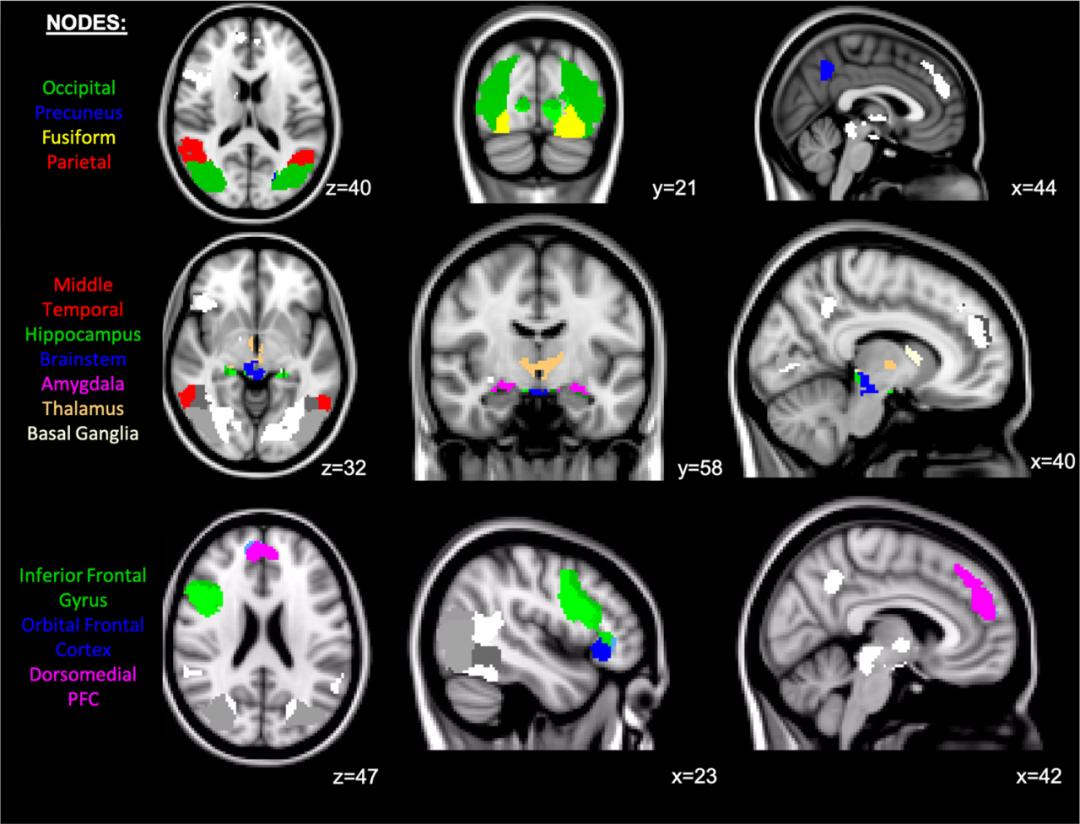

在负面图片观看期间,MDD患者的杏仁核、基底神经节、丘脑、眶额叶皮层、额下回及背内侧前额叶皮层(inferior frontal gyrus, IFG; dorsomedial prefrontal cortex, dmPFC)表现出了显著的海马体抑制迹象。MDD相关的连接性与中缝5-HT1A结合无关。然而,杏仁核、丘脑、IFG及dmPFC中更强的海马体抑制作用与海马体的5-HT1A结合有关。海马体5-HT1A结合和海马体抑制网络之间的相关性只存在于MDD患者中,健康志愿者(healthy volunteers, HV)中则无此现象。MDD组与HV组在中缝及海马体5-HT1A结合之间的相关性方面也有所不同,此相关在HV中更为明显。

对负面图片及中性图片产生反应的团簇可归纳为13个节点